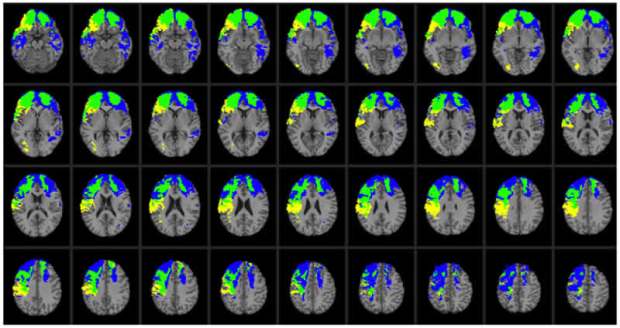

Earlier research showed that progranulin levels were elevated near plaques in the brains of patients with Alzheimer’s disease, but it was unknown whether this effect counteracted or exacerbated neurodegeneration. This image is for illustrative purposes only. Credit NIH.